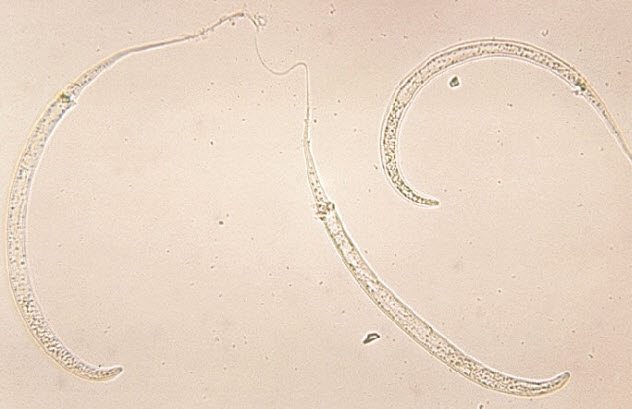

Guinea Worm:-

This particular parasitic worm’s larvae enter the bodies of their host humans via drinking water from rivers, lakes and ponds and upon entering in digestive system can cause horrifying disease.

Inside digestive system, male and female larva passes through thin intestinal lines and mate. Males die but female move up to the position under the skin mostly in the region of lower legs. There they can grow up to 30 inches in length.

After one year, female comes out of the skin inch by inch causing immense pain which leads to people often taking bath in open water and an opportunity for female to release millions of eggs again.

Since 1980’s WHO (World Health Organization) due to the atrocities of this organism, started their efforts to eradicate Guinea Worm from face of the earth. Their efforts have been somewhat fulfilled as there had been only 27 reported cases in the previous year of 2017.